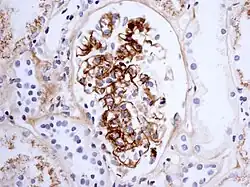

Immune complex glomerulonephritis, as seen in Henoch–Schönlein purpura; this is an example of IgA involvement in a nephropathy

The reaction can take hours, days, or even weeks to develop, depending on whether or not there is immunological memory of the precipitating antigen. Typically, clinical features emerge a week following initial antigen challenge, when the deposited immune complexes can precipitate an inflammatory response. Because of the nature of the antibody aggregation, tissues that are associated with blood filtration at considerable osmotic and hydrostatic gradient (e.g. sites of urinary and synovial fluid formation, kidney glomeruli and joint tissues respectively) bear the brunt of the damage. Hence, vasculitis, glomerulonephritis and arthritis are commonly associated conditions as a result of type III hypersensitivity responses.[11]

As observed under methods of histopathology, acute necrotizing vasculitis within the affected tissues is observed concomitant to neutrophilic infiltration, along with notable eosinophilic deposition (fibrinoid necrosis). Often, immunofluorescence microscopy can be used to visualize the immune complexes.[11] Skin response to hypersensitivity of this type is referred to as an Arthus reaction and is characterized by local erythema and some induration. Platelet aggregation, especially in microvasculature, can cause localized clot formation, leading to blotchy hemorrhages. This typifies the response to injection of foreign antigen sufficient to lead to the condition of serum sickness.[12]